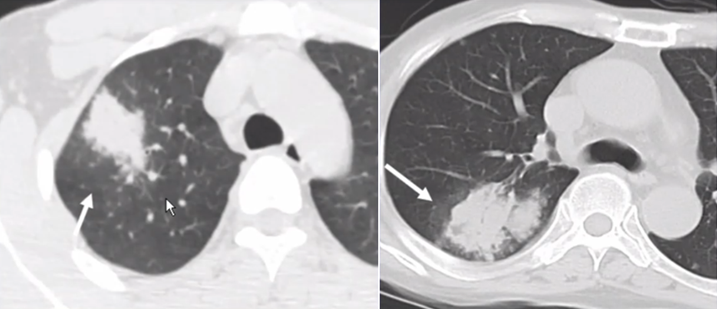

曲霉的破坏程度与曲霉菌丝生长相对成比例,其破坏范围形成的坏死、空洞及分隔均少于毛霉,而毛霉的破坏力更强。下图是一个结节,周边有晕征,说明病变是血管侵袭性,其中有很多小气泡,没有液平面,说明有菌丝的存在,菌丝固定了坏死物。但纵隔窗看到分隔特别粗大,小气泡特别大,说明坏死占的比例更多,坏死程度更严重,而菌丝的生长与坏死程度不成比例,所以是“坏死多菌丝少”,这是毛霉的特征。而曲霉感染则是“坏死多菌丝多”,坏死物相对固定,小气泡并未形成大的空洞。这也是曲霉和毛霉重要的鉴别点(图22)

图片

图22  毛霉和曲霉感染坏死、空洞的区别

注:A、B为毛霉所致病变,空洞内分隔粗大不均,空洞更大;C为曲霉所致坏死物固定,小气泡多。